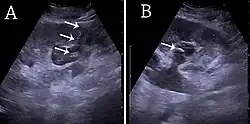

Figure 5. Simple renal cyst with posterior enhancement in an adult kidney. Measurement of kidney length on the US image is illustrated by '+' and a dashed line.[1] -

Figure 6. Complex cyst with thickened walls and membranes in the lower pole of an adult kidney. Measurements of kidney length and the complex cyst on the US image are illustrated by '+' and dashed lines.[1] -

Masses are seen as a distortion of the normal renal architecture. Most renal masses are simple cortical renal cysts with a round appearance and a smooth thin capsule encompassing anechoic fluid. The incidence increases with age, as at least 50% of people above the age of 50 have a simple cyst in one of the kidneys. Cysts cause posterior enhancement as a consequence of reduced attenuation of the ultrasound within the cyst fluid (Figure 5). The simple cyst is a benign lesion, which does not require further evaluation.[1]

Complex cysts can have membranes dividing the fluid-filled center with internal echoes, calcifications or irregular thickened walls. The complex cyst can be further evaluated with Doppler US, and for Bosniak classification and follow-up of complex cysts, either contrast-enhanced ultrasound (CEUS) or contrast CT is used (Figure 6). The Bosniak classification is divided into four groups going from I, corresponding to a simple cyst, to IV, corresponding to a cyst with solid parts and an 85–100% risk of malignancy.[1] In polycystic kidney disease, multiple cysts of varying size in close contact with each other are seen filling virtually the entire renal region. In advanced stages of this disease, the kidneys are enlarged with a lack of corticomedullary differentiation (Figure 7).[1]